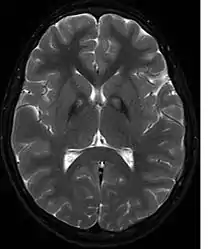

A neurological examination would show evidence of muscle rigidity; weakness; and abnormal postures, movements, and tremors. If other family members are also affected, this may help determine the diagnosis. Genetic tests can confirm an abnormal gene causing the disease. However, this test is not yet widely available. Other movement disorders and diseases must be ruled out. Individuals exhibiting any of the above listed symptoms are often tested using MRI (Magnetic Resonance Imaging) for a number of neuro-related disorders. An MRI usually shows iron deposits in the basal ganglia. Development of diagnostic criteria continues in the hope of further separating PKAN from other forms of neurodegenerative diseases featuring NBIA.

Microscopic features of PKAN include high levels of iron in the globus pallidus and the pars reticulata of substantia nigra, evident as a characteristic rust-brown discoloration[6] in a pattern called the eye-of-the-tiger sign;[7] lipofuscin and neuromelanin concentrated in the iron-accumulating areas; oval, nonnucleated structures representing swollen axons whose cytoplasm swells with vacuoles, referred to as spheroids, axon schollen, or neuroaxonal dystrophy; and Lewy bodies.[6]

Diagnosis of PKAN hit a milestone with the availability of MRIs, as well as the in-depth descriptions of those MRIs provided by Littrup and Gebarski (1985),[14] Tanfani et al. (1987),[15] Sethi et al. (1988),[16] Angelini et al. (1992),[17] Casteels et al. (1994),[18] and Malandrini et al. (1995).[19] The gene was localized to chromosome 20p by Taylor et al. (1996) [20] who suggested that this disorder should be referred to as neurodegeneration with brain iron accumulation (NBIA1) to avoid the objectionable eponym[21] of Hallervorden-Spatz. The disease was renamed 'pantothenate kinase-associated neurodegeneration' or PKAN by Zhou et al. (2001)[2] who suggested the name to avoid misinterpretation and to better reflect the true nature of the disorder. Most recently Pellecchia et al. (2005) published a report of 16 patients afflicted with PKAN, confirmed by genetic analysis.[22]